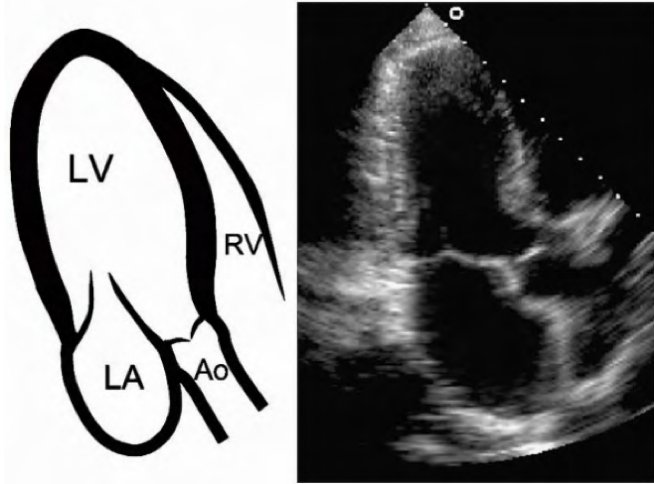

Parasternal Long Axis:

Left lateral decubitus

3rd L intercostal space. Move⬆️or⬇️ to find window

👀descending aorta, coronary sinus, pericardium, LV, both leaflets of MV, LA, aortic valve & root, RV